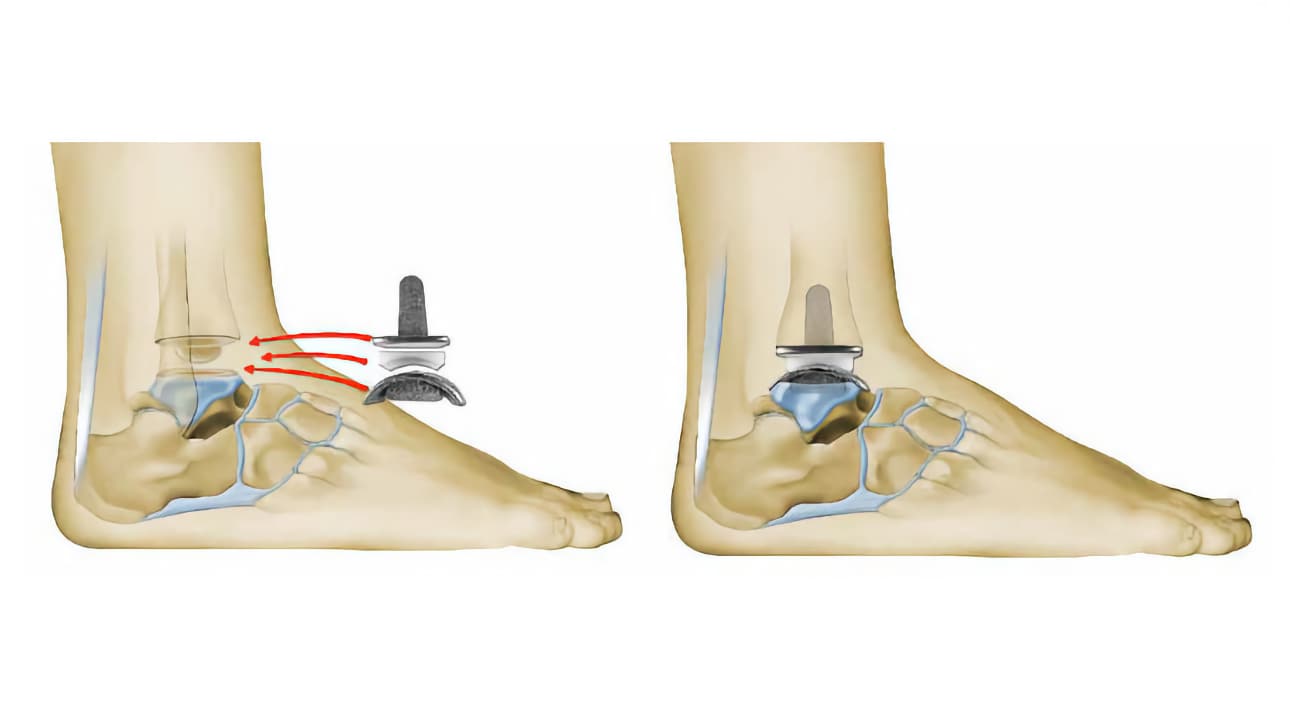

Ο χειρουργός, στη συνέχεια, τοποθετεί δοκιμαστική πρόθεση, για να δοκιμάσει τις διάφορες κινήσεις της άρθρωσης.

Μπορεί να χρειαστούν, κάποιες διορθωτικές κινήσεις πριν την τοποθέτηση της τελικής πρόθεσης.

Το τμήμα, που τοποθετείται στην κνήμη περιλαμβάνει ένα είδος μικρού στελέχους. Η άλλη του άκρη είναι επίπεδη και οριζόντια.

Το τμήμα της πρόθεσης, που εισάγεται στον αστράγαλο μπορεί να στερεωθεί με τη χρήση βιδών ή ενός είδους μικρών βελόνων. Το σχήμα του είναι ανάλογο του φυσικού αστραγάλου.

Ανάμεσα σε αυτά τα δύο μεταλλικά τμήματα, ο χειρουργός τοποθετεί ένα πλαστικό τμήμα (ένθεμα). Αναπαράγονται ακριβώς οι φυσιολογικές κινήσεις της άρθρωσης.